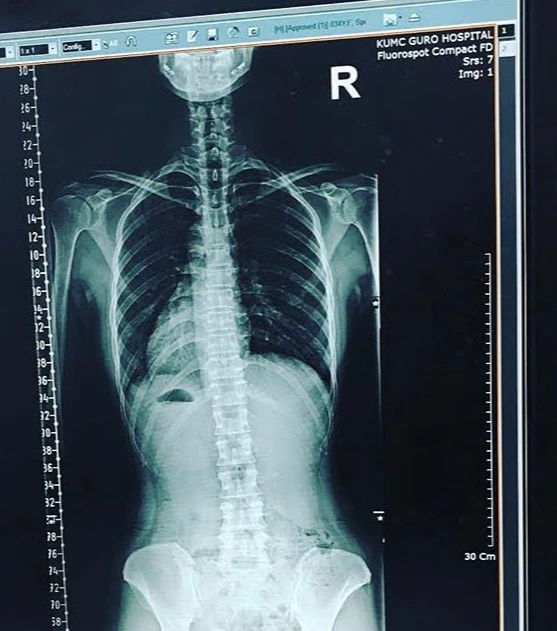

나는 그때부터 각종 병원을 돌아다니다 대학병원까지 가고서야 원인을 찾았다.

나는 천장관절증후군을 진단받았다. 다시는 과한 스트레칭은 피해야 한다고 다른 치료방법은 딱히 없다는 말을 들었다. 그 뒤로 나는 내 몸을 돌보는 여정을 시작했다. 그 여정이 12년이 또 흘렀다.

실제 치료받던 시절 나의 척추